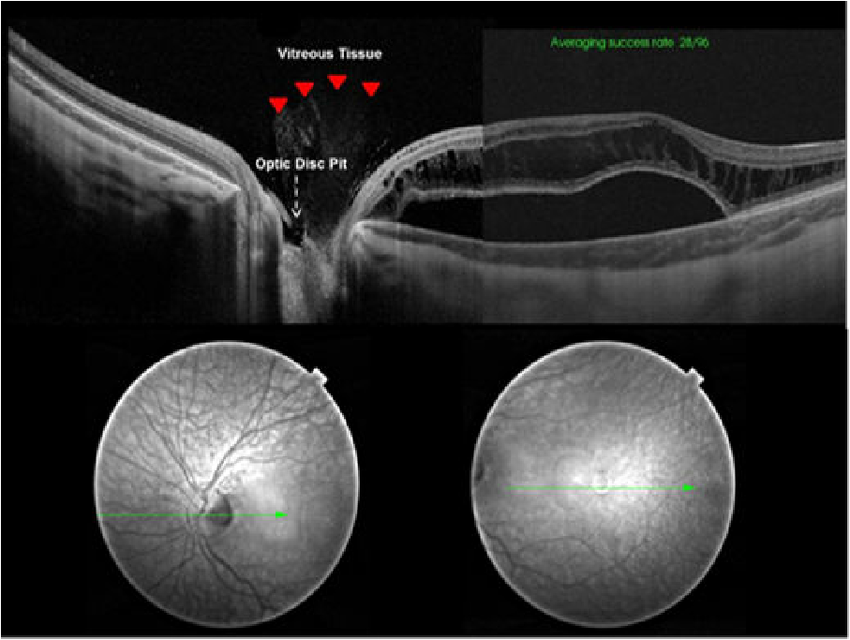

<Congenital Optic disc pit 과의 차이>

Optic disc에 발생하는 구덩이 Pit 이 선천적으로 태어날때부터 가지는 경우가 있습니다.

약 1/10,000의 유병률을 가지며, 일측성으로 단안에서만 발생하는 경우가 80% 이상입니다.

이를 Congenital optic disc pit이라고하는데, 이는 실제로 disc 에 구멍이 나있고

그구멍이 시신경 주위를 둘러싸고 있는 뇌척수액(CSF)과 연결되어있습니다.

이로인해서 Pit 구멍을 통해 CSF leakage 가 발생하면서, 그 액들이 망막하 공간으로 고이면서,

망막박리, 망막하액으로 이어지는 경우가 약 40% 에 해당하는 경우입니다.

반면, APON 은 나이가들면서 발생하는 질환으로,

Congenital pit 과 대비하여, 사상판(laminar cribrosa)조직이 보일정도로 깊은 구덩이기는 하지만,

그 구덩이가 뇌척수액과는 연결되지 않습니다.

그래서 이러한 특징으로 인해, 망막하액이 동반되지는 않기에,

가짜구덩이라는 의미로, Pseudopit이라고도 합니다.